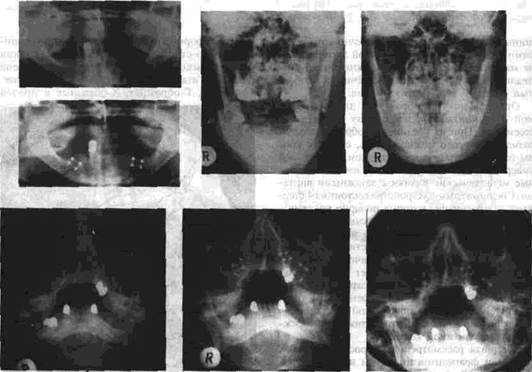

Рис 54 (1-7) иллюстрирует возможность прочного соединения отломков нижней и верхней челюстей с помощью мини пластинок из титана На рис 55 показан комплект мини-пластинок и набор инструментов, необходимых для осуществления остеосинтеза с помощью этих плас

1,2- рентгенограммы нижней челюсти до и после остеосинтеза (по поводу двустороннего перелома тела нижней челюсти без смещения ее отломков) с применением мини пластинок, 3, 4 -- рентгенограммы до и после двустороннего перелома в области углов нижней челюсти, 5, 6 - до и после перелома, а 7 - спустя 6 месяцев после остеосинтеза с использованием мини-пластинок